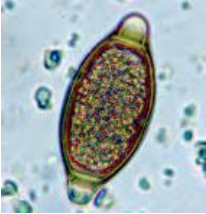

Um levantamento sobre disposição de esgotos domésticos no rio que recorta a cidade detectou na análise parasitológica a seguinte estrutura:

Podemos afirmar, de acordo com a figura, que se trata de um